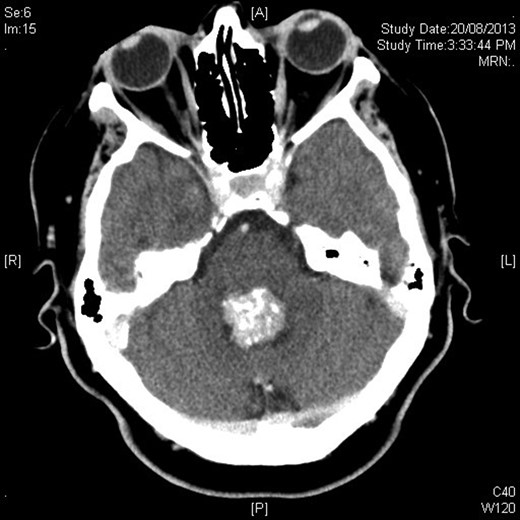

Mrs MM is a 62-year-old female who presented to our institution complaining of a 4-day history of nausea, vomiting and speech difficulties. She initially presented to a peripheral hospital following a fall at home and underwent workup for this. Clinically she scored a Glasgow Coma Scale (GCS) of 14 due to her confusion but had normal strength in all of her limbs. Initial computed tomography brain revealed a 2.6 × 2.5 × 2.1 cm rounded masses enhancing with contrast with areas of calcification in the fourth ventricle and obstructive hydrocephalus (Figs 1 and 2). The following day she underwent magnetic resonance imaging (MRI) brain showed the lesion to be isodense on T1-weighted imaging mildly hypodense on T2-weighted imaging (Fig. 3), and there was no other pathology demonstrated apart from chronic microvascular ischemic changes.

Sagittal figure contrast-enhanced CT brain showing intimate relationship to choroid plexus and associated ventricular dilatation.